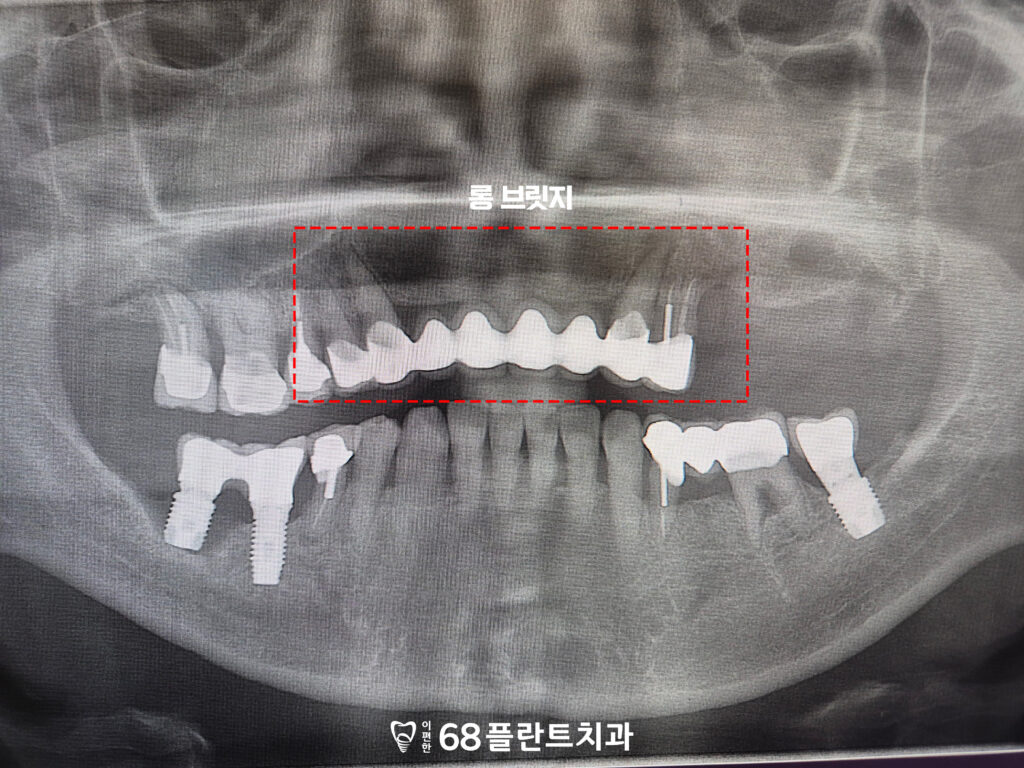

마지막으로 위쪽의 롱 브릿지도

힘을 받고 있는 지대치쪽으로 잇몸뼈가 소실되어,

브릿지의 안정성이

크게 떨어지고 있었습니다.

이로 인해 지대치가 치아를

제대로 지탱하지 못하게 되었고,

브릿지의 기능에도 영향을 미쳐

불편함이 지속되었습니다.

결국, 이 부분 역시 임플란트로 교체하여

보다 안정적이고 기능적인 해결을

진행하기로 하였습니다.

롱브릿지 부분도 임플란트를 식립하여

기존의 브릿지가 받던 하중을

분산시킬 수 있도록 했습니다.